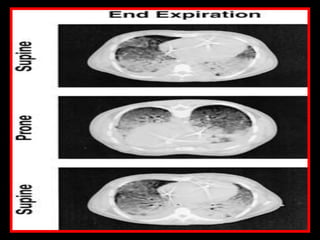

Spectrum of Regional Opening Pressures

(Supine Position)

Superimposed

Pressure Inflated 0

Alveolar Collapse

(Reabsorption) 20-60 cmH2O

Small Airway

Collapse

10-20 cmH2O

Consolidation 